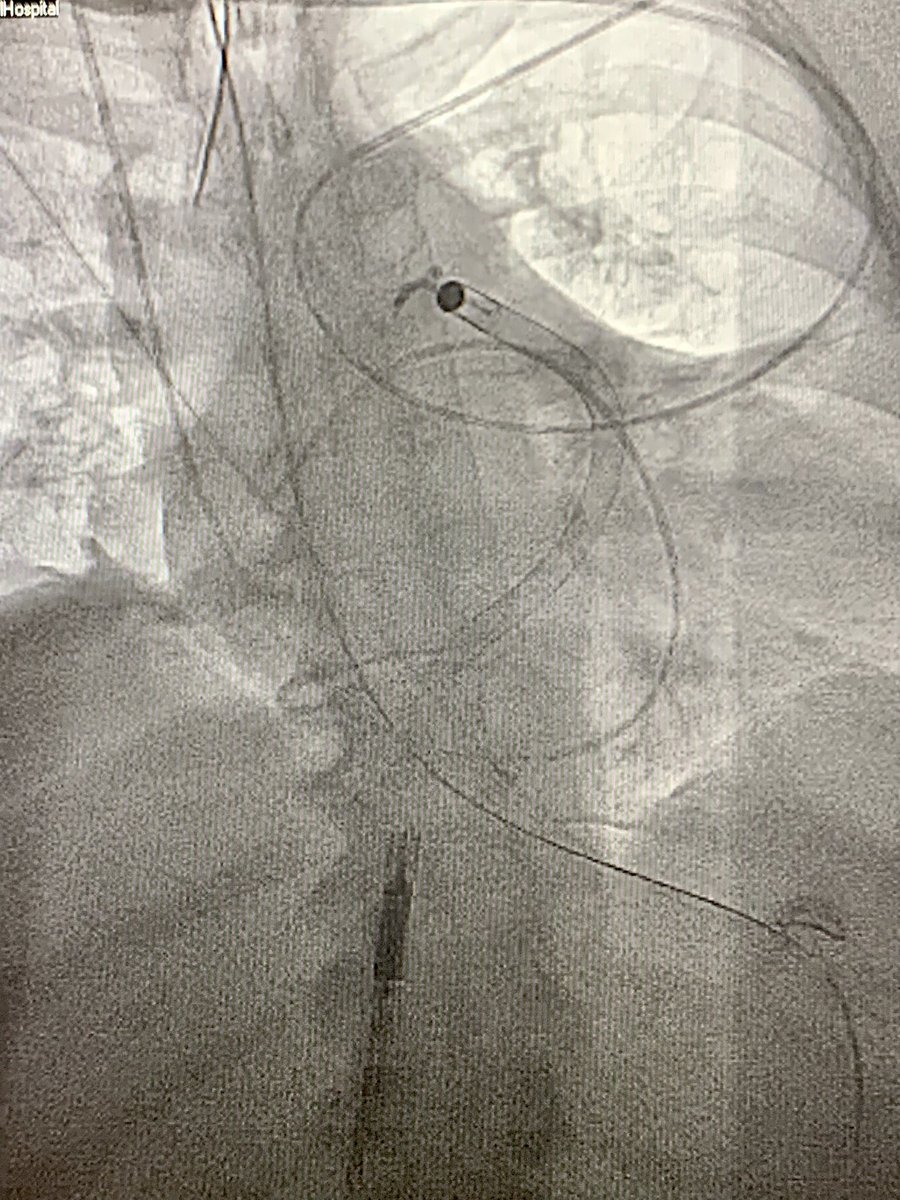

Severe AS by TEE (MG 60 mmHg). INR 1.9. Wasn’t planning on crossing the valve but JR popped across (luck). We don’t have 4F PIG. In age of no Langston made due with what I had! Right radial 6F MB1 guide with mother daughter 4F vert. MG on cath 52 mmHg. #CathLabHack #Cardiotwitter

DrJayMohan's tweet image. Severe AS by TEE (MG 60 mmHg). INR 1.9. Wasn’t planning on crossing the valve but JR popped across (luck). We don’t have 4F PIG. In age of no Langston made due with what I had! Right radial 6F MB1 guide with mother daughter 4F vert. MG on cath 52 mmHg. #CathLabHack #Cardiotwitter